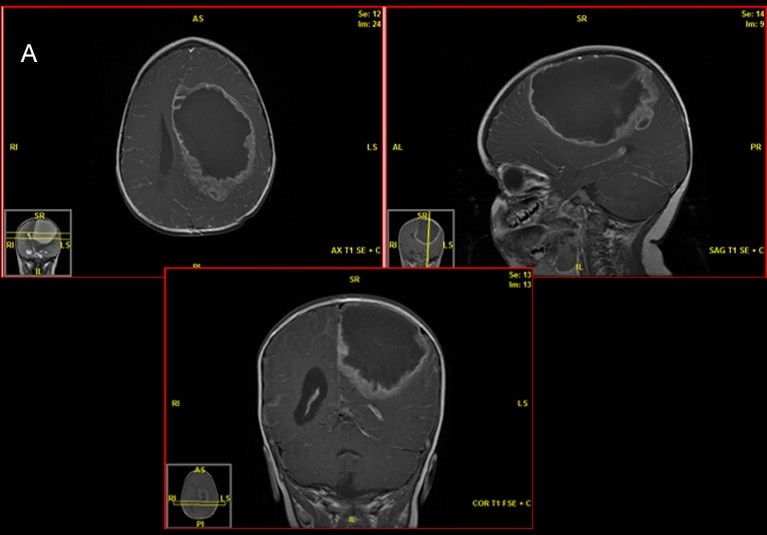

الورم البطاني العصبي مرتفع الدرجة

يُظهر التصوير بالرنين المغناطيسي الذي أُجري قبل الجراحة ورمًا بطانيًا عصبيًا مرتفع الدرجة لدى مريض يبلغ من العمر 18 شهرًا.